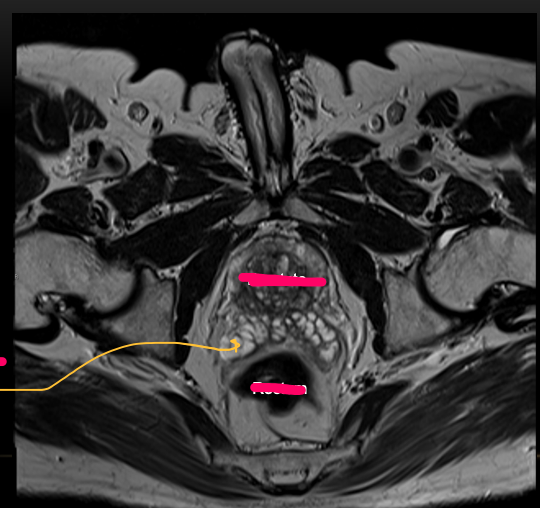

Q

Axial MRI